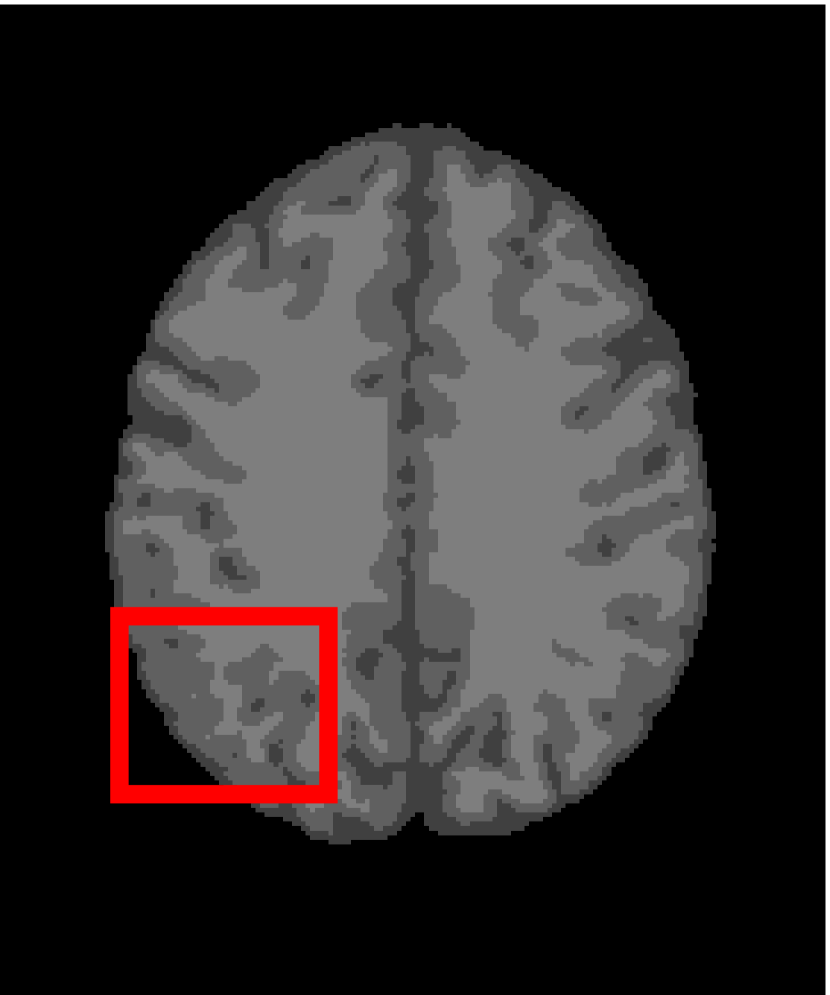

Next, we representatively segment five medical images from BrianWeb. They are represented as five slices in the axial plane with a sequence of 70, 80, 90, 100 and 110, which are generated by T1 modality with slice thickness of 1mm resolution, 9% noise and 20% intensity non-uniformity. Here, we set c=4𝑐4c=4 for all cases. The comparison between WRFCM and its peers are shown in Fig. 9 and Table II. The best values are in bold.

Figure 9: Segmentation results on five medical images. The parameter: ϕ=5.35italic-ϕ5.35\phi=5.35. From top to bottom: noisy images, ground truth, and results of FCM_S1, FCM_S2, FLICM, KWFLICM, FRFCM, WFCM, DSFCM_N, and WRFCM.

By a view of the marked red square in Fig. 9, we find that FCM_S1, FCM_S2, FLICM, KWFLICM and DSFCM_N are vulnerable to noise and intensity non-uniformity. They give rise to the change of topological shapes to some extent. Unlike them, FRFCM and WFCM achieve sufficient noise removal. However, they produce overly smooth contours. Compared with its seven peers, WRFCM can not only suppress noise adequately but also acquire accurate contours. Moreover, it yields the visual result closer to ground truth than its peers. As Table II shows, WRFCM obtains optimal SA, SDS and MCC results for all five medical images. As a conclusion, it outperforms its peers visually and quantitatively.